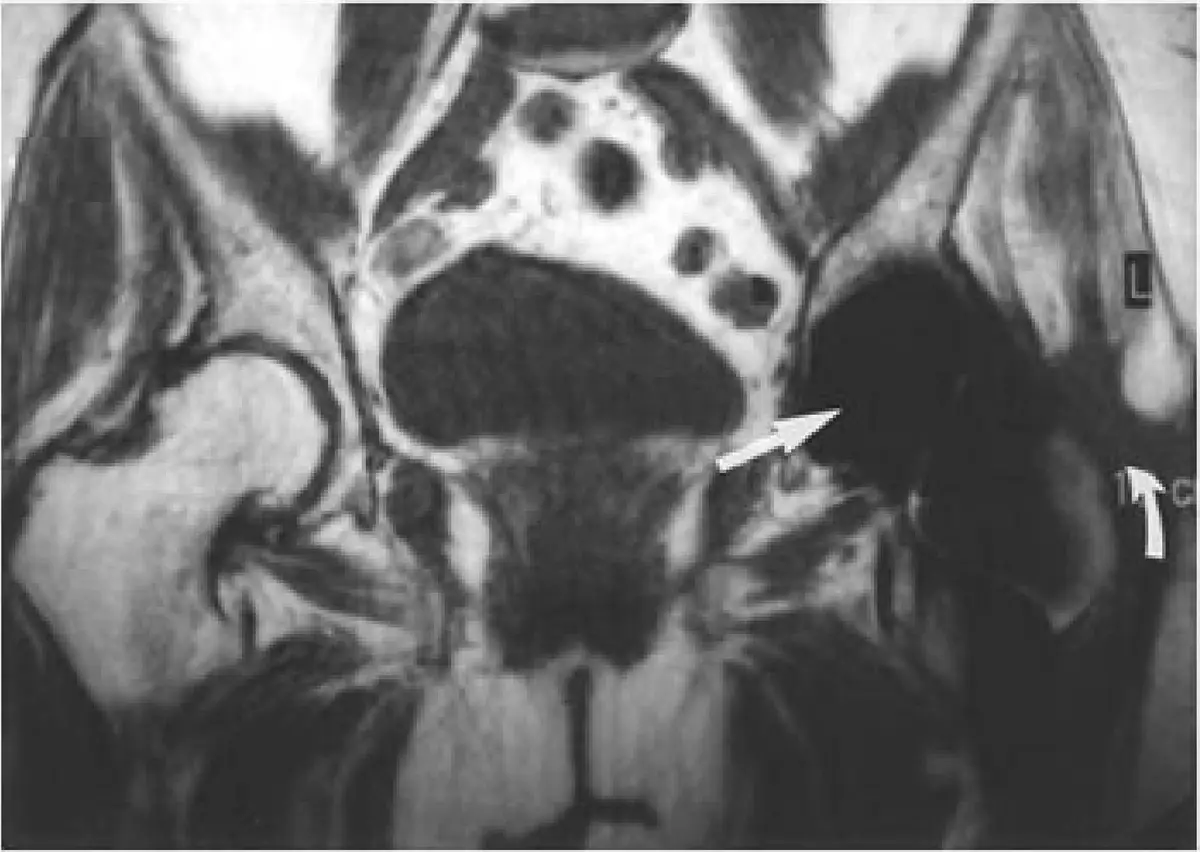

附圖為骨盆(pelvis)冠狀位(coronal)MRI 影像,顯示雙側髖關節及骨盆結構。圖中有一白色箭號,指向左側髖關節(left hip joint)附近的特定異常:

- 局部訊號缺失(signal void):箭號所指區域呈現明顯的黑色低訊號/無訊號區,且該無訊號區域的範圍遠大於正常解剖結構應有的大小,這是感磁性偽影典型的「blooming」效應——金屬物體周圍局部磁場不均勻導致 T2* 去相(dephasing),造成訊號缺失範圍大於實際金屬尺寸。

- 幾何扭曲(geometric distortion):箭號附近的解剖結構邊緣出現扭曲,周邊信號分布不均勻,符合局部 B0 場不均勻的表現。

- 位置特徵:偽影位於髖關節附近,高度提示金屬植入物(如髖關節置換術的股骨頭假體或骨固定器材)是偽